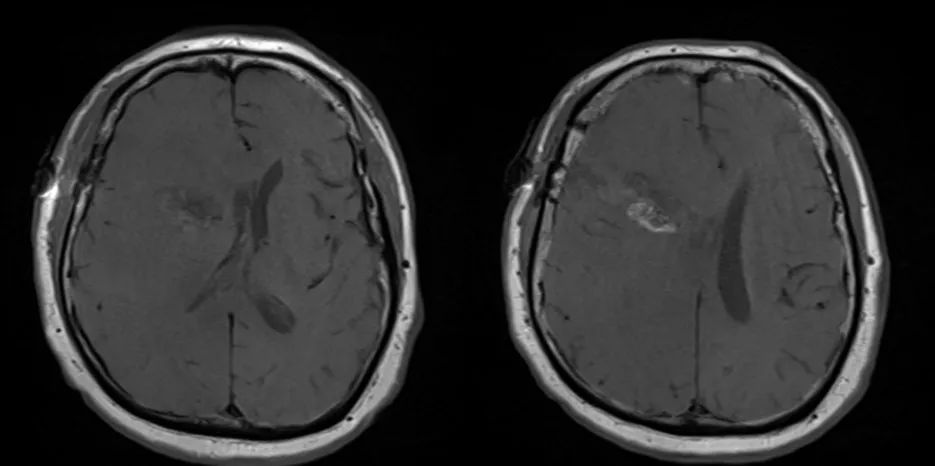

立体定向导航下行右额开颅。 鉴于肿瘤位置深,计划在60mm长BrainPath(厂家NICO)管型牵开器辅助下以微侵袭方式切除该肿瘤。 术前借助导航系统于右侧额叶寻找对应肿瘤长轴的脑沟并以此为进入点确定术中路径,手术通道与肿瘤长轴平行可以有效降低纤维传导束和基底节的损伤风险。

右额开颅最重要的注意事项就是骨瓣应该位于冠状缝前方以防误伤中央前回。 如果患者为左利手,应避开额下回,尤其三角部和盖部,以免损伤Broca区。 肿瘤尾端侵犯尾状核、内囊前肢和侧脑室额角,部分肿瘤已经毗邻室间孔,因此可能与穹窿、丘纹静脉和尾状核静脉关系密切。

术后患者安返神经ICU。 术后使用地塞米松并于1周内迅速减量撤药。 使用左乙拉西坦500mg bid预防性抗癫痫。 术后第1天复查MRI见肿瘤近全切。